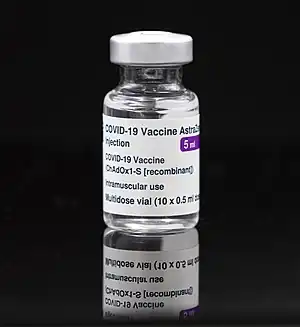

Adenovirus have been used to produce viral vector COVID-19 vaccines. "In four candidate COVID-19 vaccines... Ad5... serves as the 'vector' to transport the surface protein gene of SARS-CoV-2".[91] The goal is to genetically express the spike glycoprotein of severe acute respiratory syndrome coronavirus 2 (SARS-CoV-2). A replication-deficient chimpanzee adenovirus vaccine vector (ChAdOx1) is used by the Oxford–AstraZeneca COVID-19 vaccine that has been approved for use.[92][93] The Janssen COVID-19 vaccine uses modified recombinant adenovirus type-26 (Ad26).[94] Recombinant adenovirus type-5 (Ad5) are being used by Ad5-nCoV,[95] ImmunityBio and UQ-CSL V451. The Gam-COVID-Vac (aka Sputnik-V) product is innovative because an Ad26 based vaccine is used on the first day and an Ad5 vaccine is used on day 21.[94] Another one is ChAd-SARS-CoV-2-S; the vaccine reportedly prevented mice that were genetically modified to have human ACE2 (hACE2) receptors, presumably receptors that allow virus-entry into the cells, from being infected with SARS-CoV-2.[96][97]